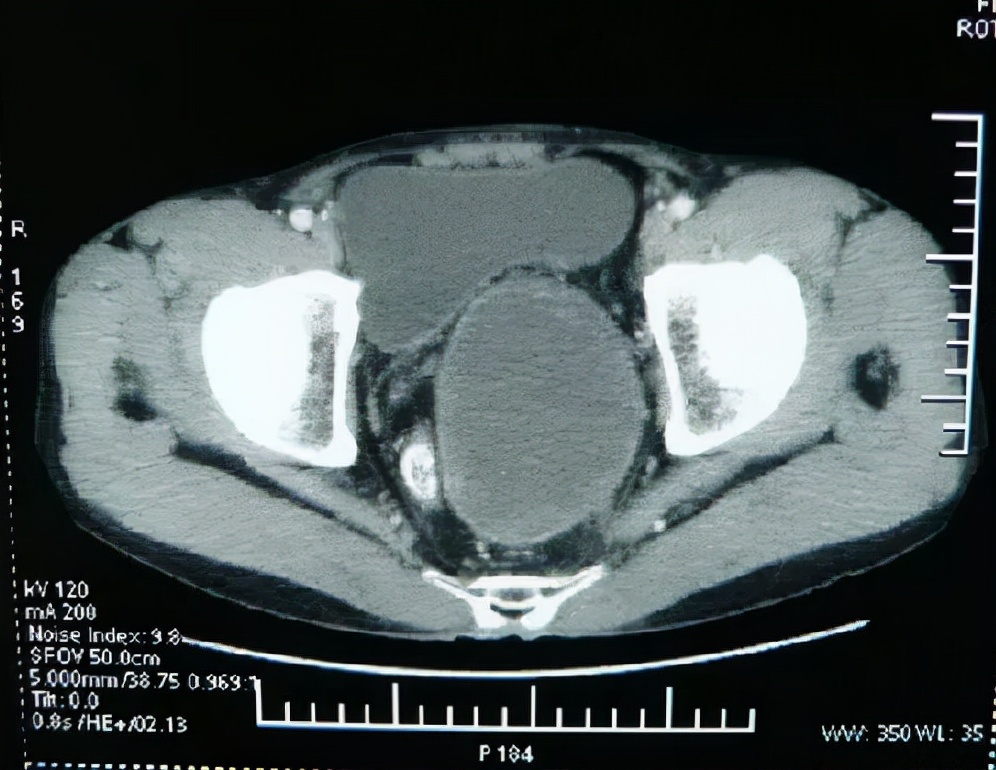

安军明主任医师介绍到,神经鞘瘤是一种神经源性肿瘤,该肿瘤是一种孤立性、有包膜、生长缓慢的肿瘤,大多为良性,偶有恶性,通常好发于头、颈部、躯干,极少情况下巨大的肿瘤位于腹膜后和盆腔。当肿瘤逐渐增大压迫临近器官时会出现一些非典型的症状,如压迫神经时,可引起腹痛、腰痛或下肢疼痛,如压迫膀胱出现尿频、解小便困难,如压迫直肠可致排便困难。当前,手术切除仍是盆腔神经鞘瘤最佳治疗手段。

段阿姨盆腔神经鞘瘤术后遗留小便*禁失**,大便困难,会阴疼痛,小腿以下疼痛麻木,按经络辨证,属于足太阳膀胱经症。足太阳膀胱经经气不利,则腰、臀部及下肢后侧疼痛,足小趾麻木不用。膀胱气化失司,则小便不利或遗尿。针灸治疗选取肾俞穴、大肠俞穴、膀胱俞穴属足太阳膀胱经,“俞”意为“通输”,有传输经气之意,而五脏六腑之气均输注于足太阳膀胱经,故针刺此三穴可调节脏腑气血。次髎穴位于第2骶后孔,会阳穴位于尾骨旁,它们的深层下方分布着S2-S4神经,针刺此二穴,可起到改善排尿排便的作用。段阿姨小腿以下疼痛麻木,行走困难,与足太阳膀胱经脉闭阻、气血运行不畅的病机符合,针刺秩边穴、委中穴、承山穴等符合经络辨证取穴原则,也体现了“经脉所过, 主治所及”的针灸诊疗特色。